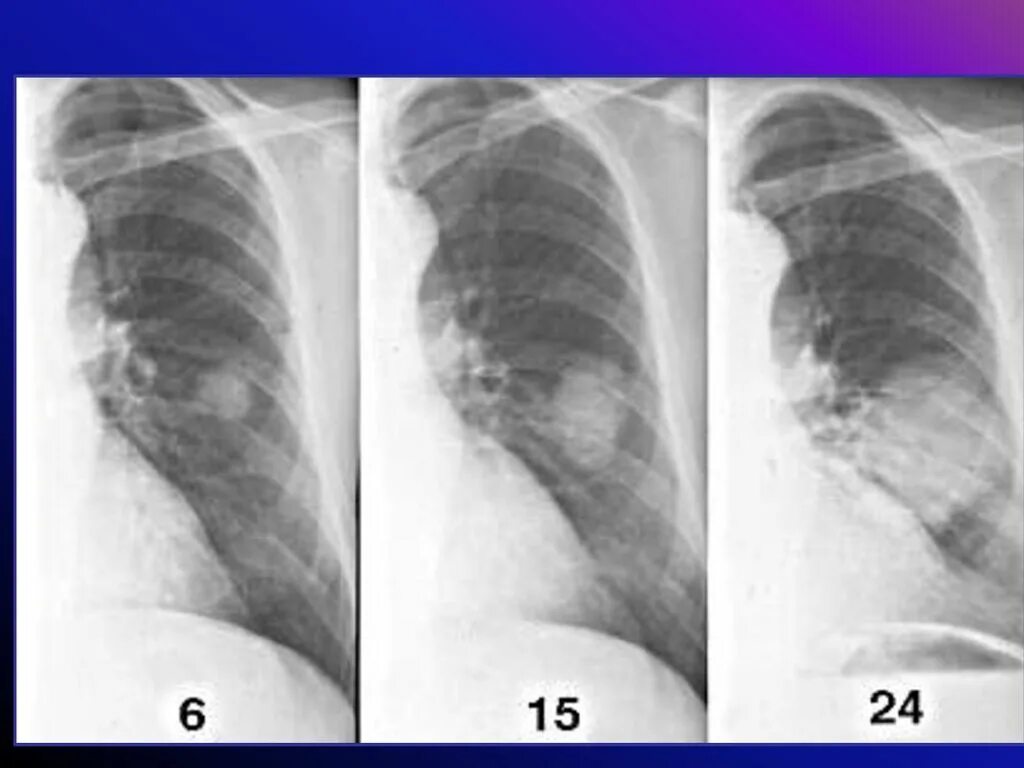

Метастазы в легкие при раке молочной